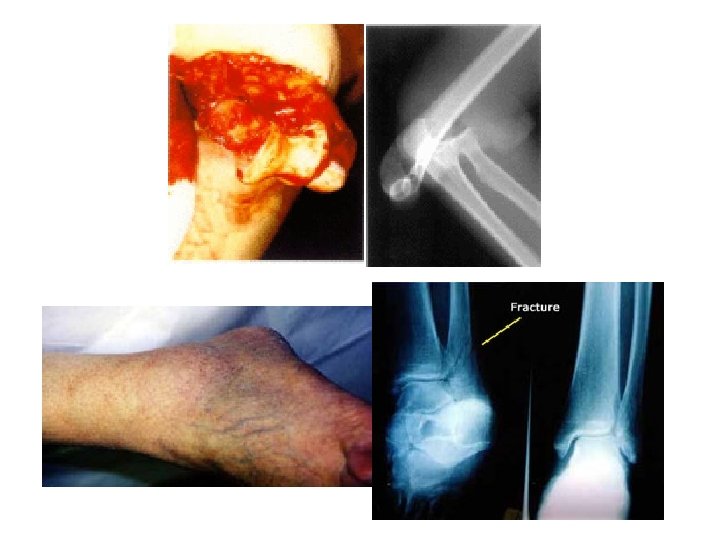

Fracture • A disruption in the integrity of a living bone involving injury to: – – Bone marrow Periosteum Adjacent soft tissues

Types of Fractures • green stick • fissured • comminuted • transverse • oblique • spiral • Pathologic • Stress • Occult

Fracture Healing – Bone is the only tissue in the human body other than liver that heals by regeneration instead of by scarring. – For regeneration to occur the bone must be immobilized to allow uninterrupted formation of new bone.

Fracture Healing • Primary healing – Non displaced fractures, fractures with compressive fixation across the fracture site – Osteoblasts traverse the fracture site and lay down lamellar bone without forming immature bone when there is direct contact between cortical bone ends • Secondary healing – No compression across fracture site, motion can occur – Fracture callus forms to stop motion, stage of consolidation and remodeling